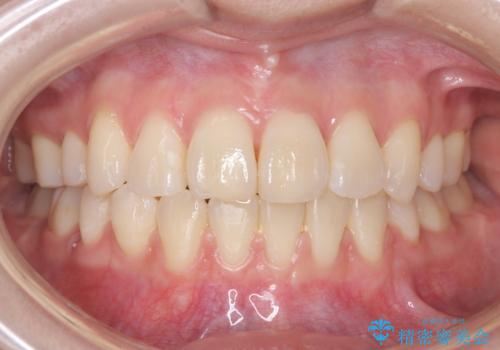

50代女性 八重歯を矯正治療 歯並びの中等度のがたつき

マウスピース矯正が煩わしい ワイヤー装置での非抜歯矯正